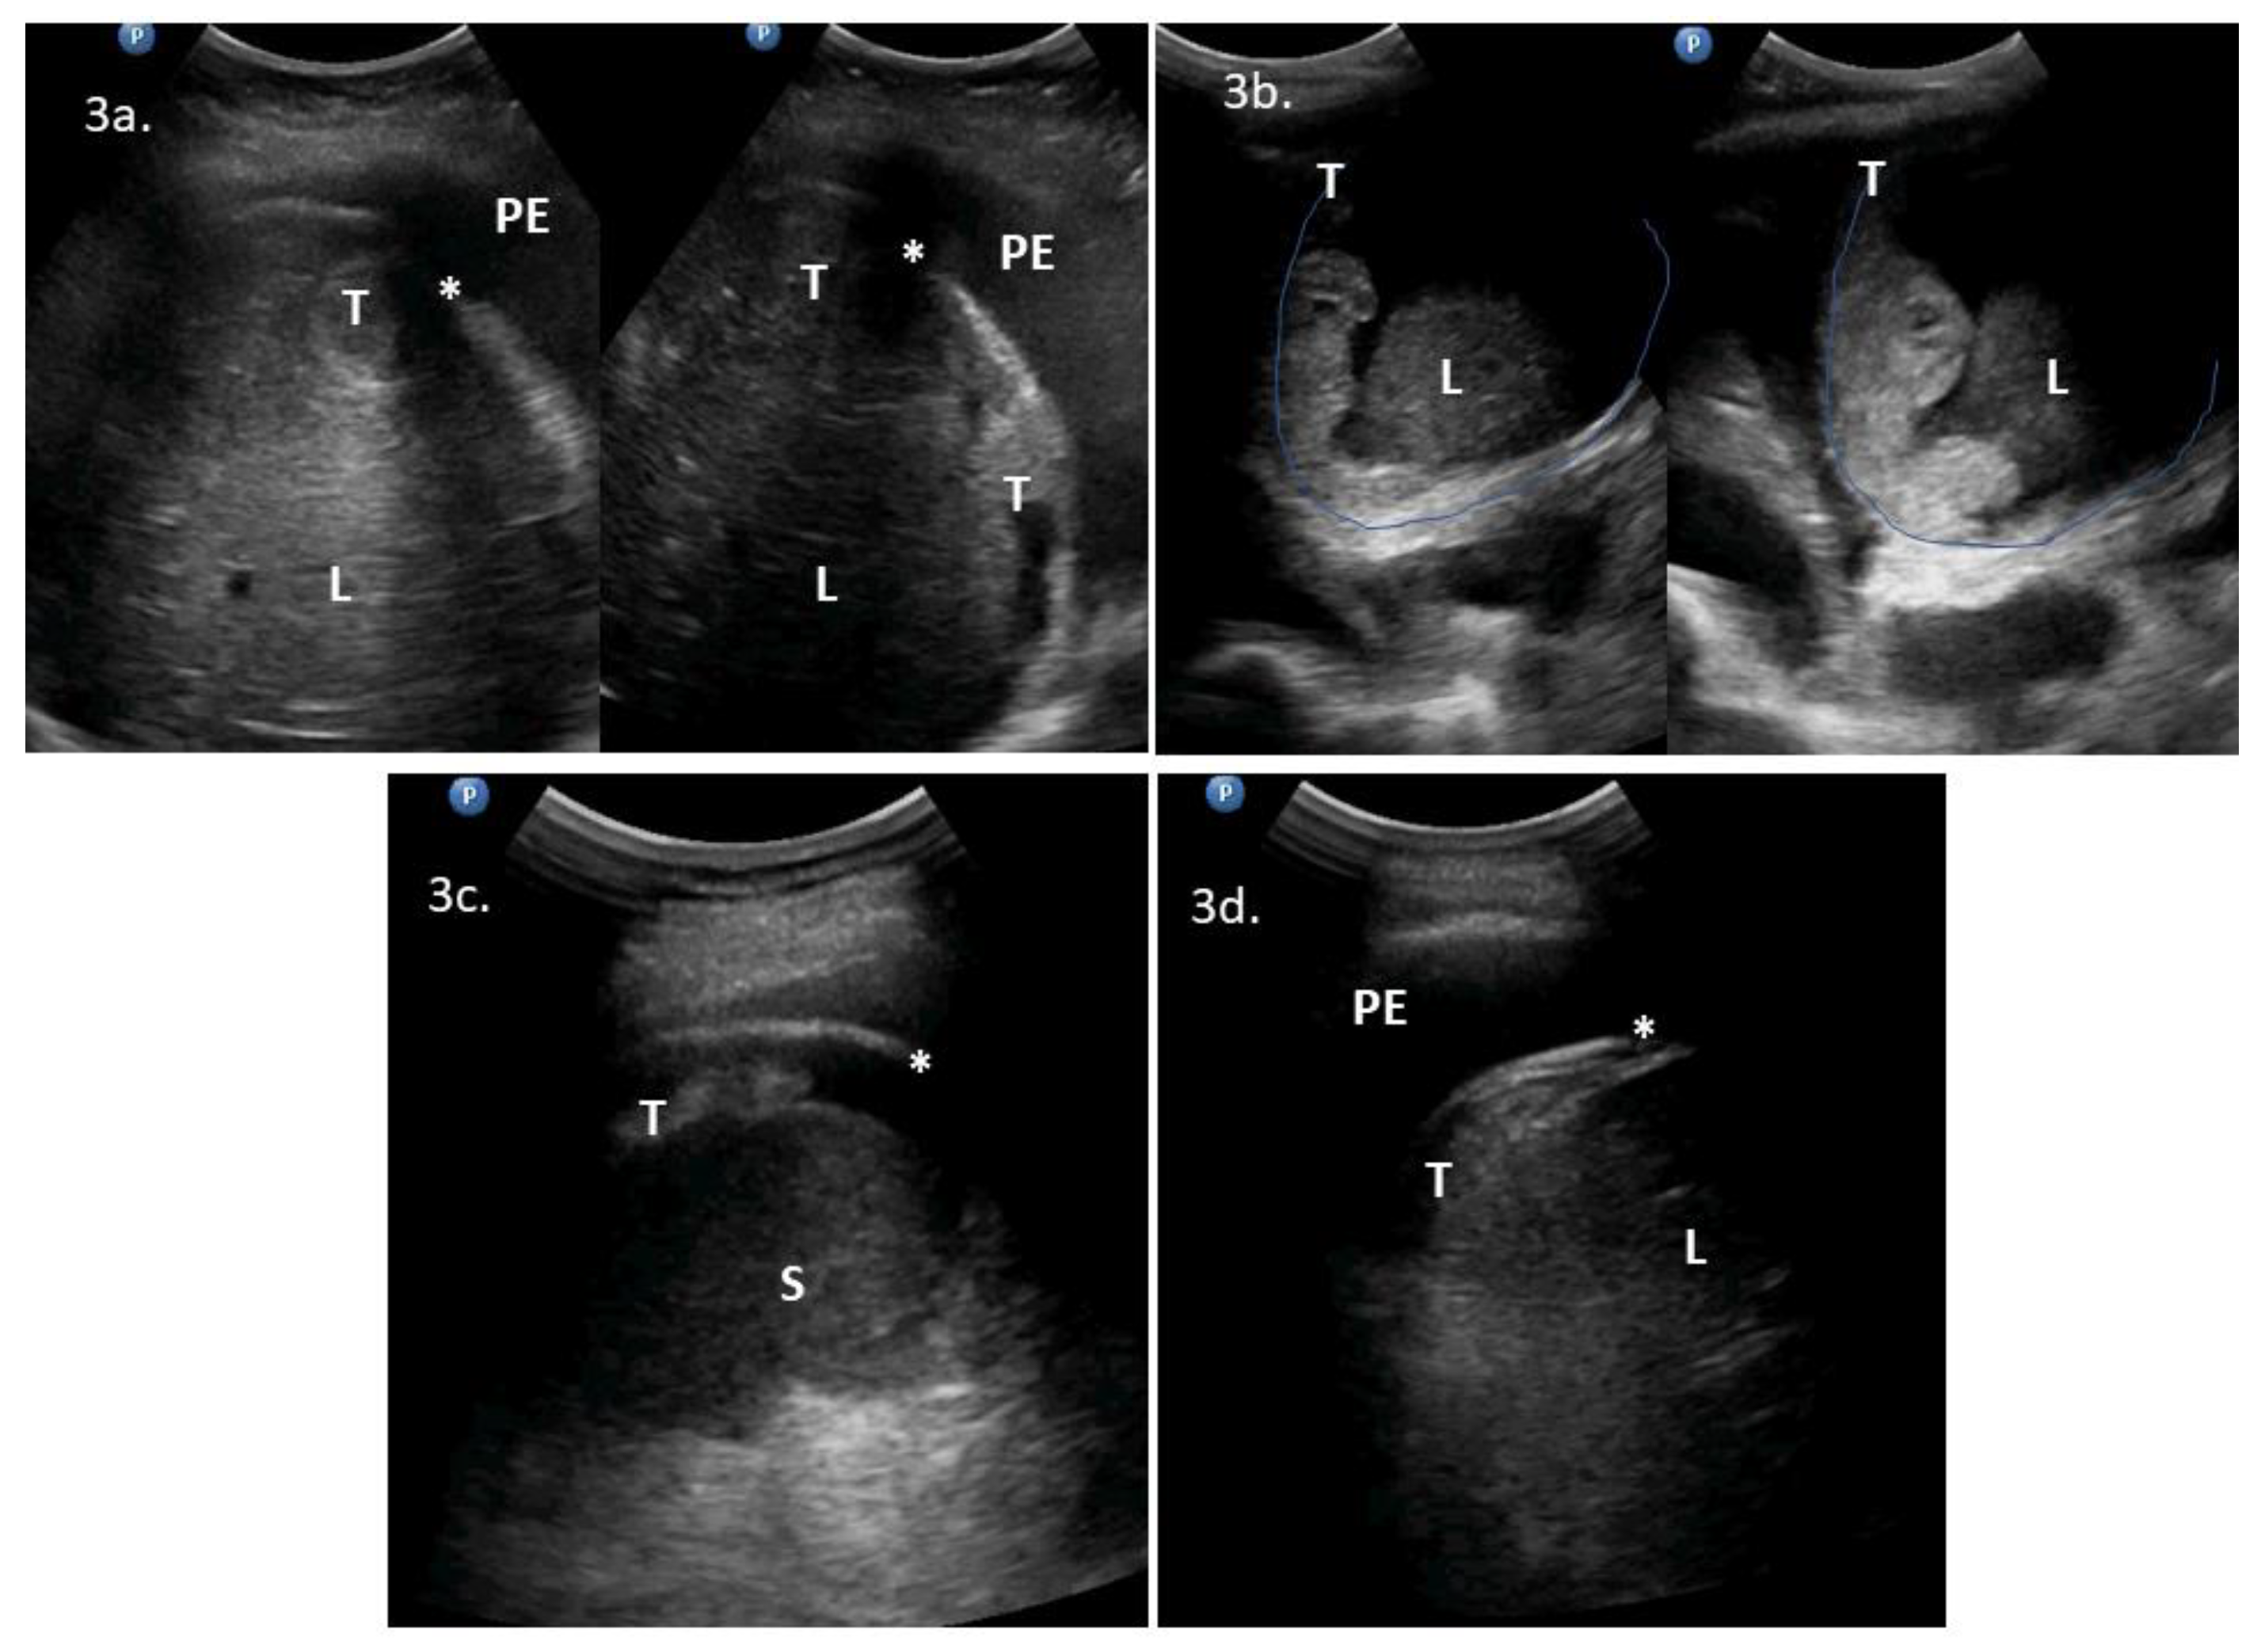

| 1 | 71 | 3 | ascites, massive pelvic involvement, omental involvement, spleen involvement | pleural diaphragm involvement *, pleural effusions | ascites, carcinomatosis, massive pelvic involvement, omental involvement, pleural effusions, spleen involvement | Yes | Yes | NoScore: 9 → 11 High → High | Could replace DLSK | 2a | DLSK, HGSOC, NACT |

| 2 | 62 | 1 | ascites, carcinomatosis, omental involvement, spleen involvement | abdominal diaphragm involvement **, pleural effusions, ligamentum teres of the liver involvement | - | Yes | Yes | YesScore: 6 → 8 Intermediate → High | Could precede PDS | 2b, VS1 | PDS attempt. HGSOC, R > 1 cm |

| 3 | 53 | 3 | ascites, massive pelvic involvement, omental involvement | abdominal diaphragm involvement **, pleural diaphragm involvement *, pleural effusions | - | Yes | Yes | YesScore: 6 → 8 Intermediate → High | No | 2c, 2d, 3a, VS2 | PDS, mucinous G3. R = microscopic |